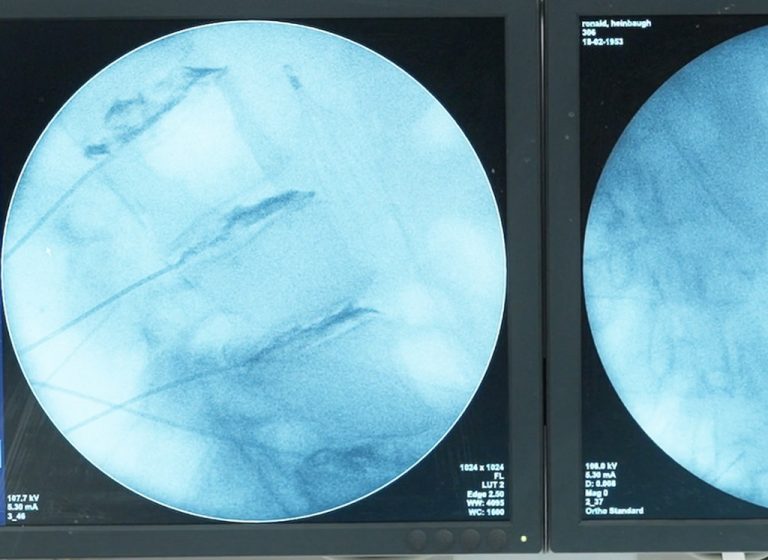

The DISCSEEL Procedure is a minimally invasive treatment designed to address the underlying causes of back pain by repairing damaged spinal discs. Back pain often results from issues like annular tears, herniated discs, or degenerative disc disease, all of which can lead to chronic discomfort and reduced mobility. By injecting a fibrin-based sealant into the affected discs, the DISCSEEL Procedure works to close tears in the outer layer of the disc, promoting natural healing and regeneration of the disc tissue. This approach not only reduces pain by preventing further disc damage and nerve irritation but also helps preserve the spine’s natural function, offering long-term relief without the need for more invasive surgeries like spinal fusion.

- Experience with intradiscal injections using fluoroscopy

- How to Perform the DISCSEEL® Procedure Through Hands-on Lumbar Lab Simulation